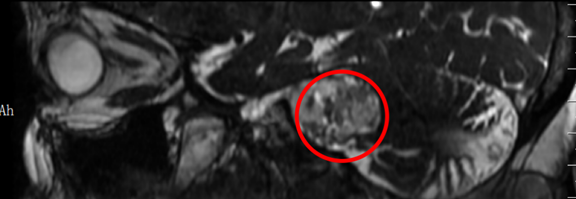

据了解,患者影像检查显示,桥前池、桥小脑角池及鞍上池存在表皮样囊肿,包绕双侧动眼神经、滑车神经、三叉神经等关键颅神经,神经结构受压移位。此类病例因操作空间受限、毗邻重要血管神经,手术风险极高,稍有不慎可能导致严重并发症,甚至危及患者生命。